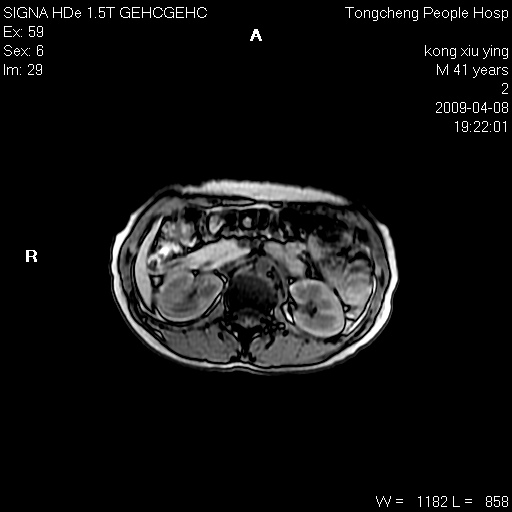

标题: CL1008:【经典】胆囊石榴籽样结石。

女,41岁。健康体检——彩超提示:胆囊显示不清。平素健康,无不适感。

腹部mr扫描及mrcp,图像如下: